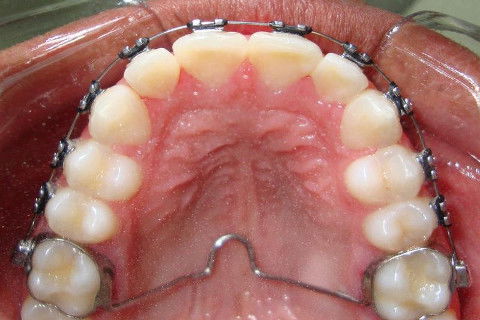

Paciente D. F. S., 19 anos, com queixa principal o apinhamento superior e inferior. Realizado o diagnóstico foi proposto duas opções de tratamento: exodontia de 04 pré-molares ou exodontia de incisivo inferior e slices superior, verticalização do molar 47 para futura instalação de implante do 46.

O paciente optou pela segunda opção, estando de acordo com as vantajens e desvantagens da terapia.

O tratameno foi iniciado com a montagem completa do aparelho superior e inferior, a indicação da exodontia do elemento 41, alinhamento e nivelamento.

Atualmente estamos com  04 meses de tratamento, podemos notar uma grande evolução no caso em pouco tempo.